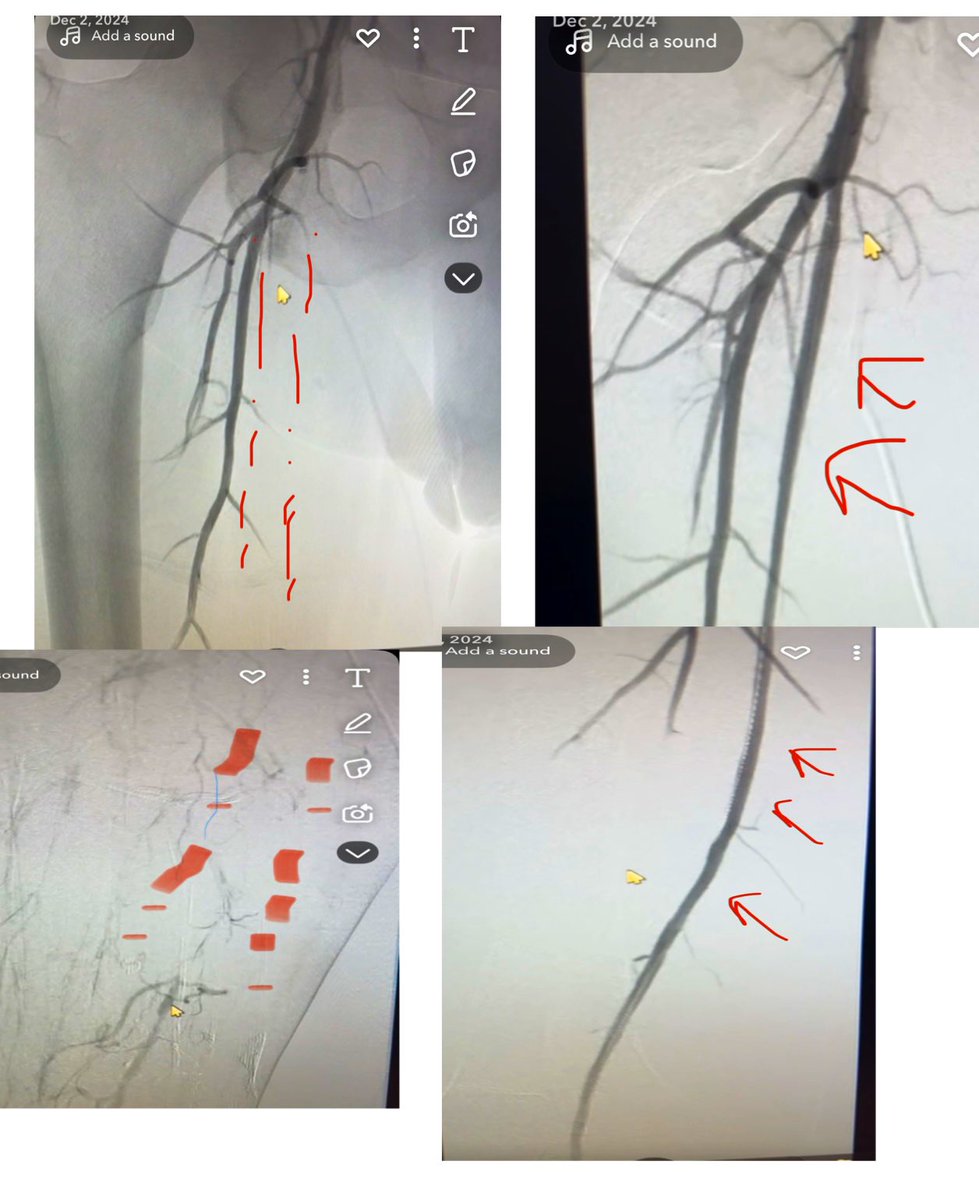

بفضل الله، ثم بكفاءة أطباء الأشعة التداخلية 💪 نجح فريق متخصص في #نجران في إنقاذ حياة شاب أصيب بمتلازمة ”وندريليش” النادرة، عبر تدخل دقيق أوقف نزيفًا خطيرًا دون جراحة. إنجاز يترجم تطور التخصص ودوره المحوري في إنقاذ الأرواح. #الأشعة_التداخلية تجمع نجران الصحي